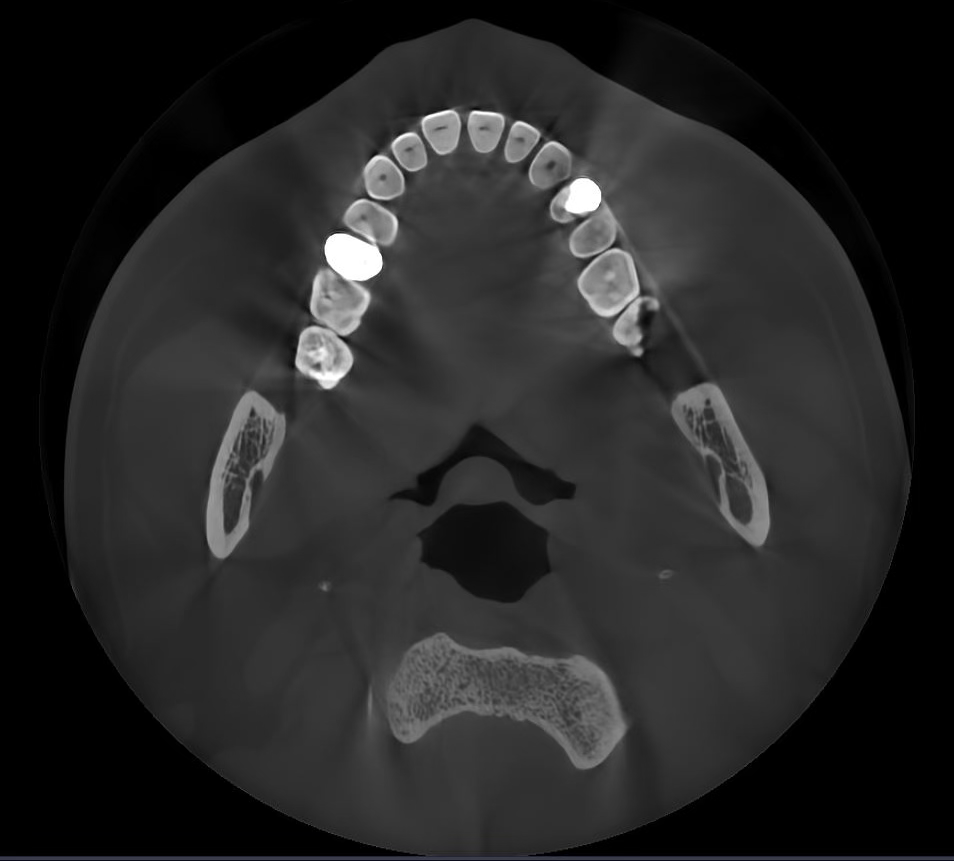

Các hiện vật kim loại được xóa bằng công nghệ AI và cấu trúc răng, mão kim loại và cấy ghép được phục hồi chính xác dựa trên các nguyên tắc toán học.

Không có MAR